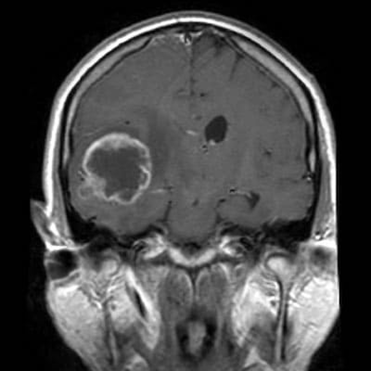

Злокачественные новообразования: Глиома

Глиомы - это менее известные опухоли, чем остальные новообразования, однако не менее опасные, даже если имеют доброкачественное течение. Например, при глиобластоме - наиболее распространённой форме глиомы (примерно 45 % всех глиом), в течение 5 лет выживают только 5 % пациентов. В целом эта группа опухолей, самые распространенные первичные опухоли головного мозга, возникающие из нейроглии, вспомогательных клеток нервной ткани. Эти клетки создают микроокружение для нейронов, обеспечивая условия для возникновения и передачи нервных импульсов, помогают питанию нейрона. Глиальные (глиоциты) и нервные клетки (нейроны) не могут существовать друг без друга, вместе образуя нервную систему - поэтому, хотя глиальные клетки являются вспомогательными, они играют очень важную роль в жизнедеятельности организма. В настоящее время увеличение выявляемости глиом связано, в первую очередь, широкому проведению диспансеризации и доступности высокотехнологичного обследования, например МРТ. Как уже было ска

В настоящее время увеличение выявляемости глиом связано, в первую очередь, широкому проведению диспансеризации и доступности высокотехнологичного обследования, например МРТ.